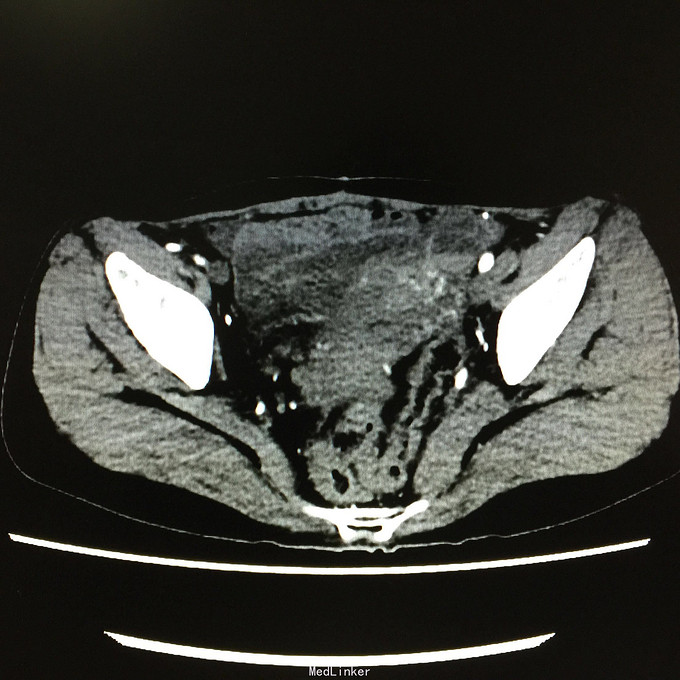

查体无特殊。 辅助检查:中下腹CT平扫+增强+CTU+CTA示:1.右输尿管中上段病变,考虑恶性病变,周围多发淋巴结转移,髂总动脉及髂外动脉起始部、髂内动脉中上段受侵闭塞,右侧腰大肌可疑受侵;建议输尿管镜检查;右肾重度积水,右肾功能明显受损。2.CTA示:右肾动脉纤细,肝右动脉起源于肠系膜上动脉。3.子宫体密度不均匀,建议MRI检查。中下腹MRI平扫+增强+MRU检查结果类似。

患者术后2月出现反复臀部疼痛,左侧为主,疼痛跑迷宫为隐痛,于翻身及活动时加重,卧床休息可稍缓解,多于下午出现,伴有发热,最高达39℃,在当地医院予“氟康唑”及止痛治疗后稍有缓解,但仍反复发热。后疼痛加剧,并出现双下肢疼痛,以大腿外侧为主,无间歇性跛行,无小腿及双足麻木疼痛不适,行对症治疗后效果不佳,于2015-10-9再次返院,予消炎止痛、营养支持及营养神经等治疗。查CT及MRI均提示骶髂关节炎症及腹膜后巨大病变,右侧髂总动脉及髂内、外动脉上段、右侧腰大肌受累。2015-10-15 14:00患者出现右下肢剧烈疼痛、右下肢乏力和麻木,随后出现2次血便,每次量约100ml,暗红色,无腹胀、腹痛等不适,查血提示白细胞 28.17*10E9/L,中性粒绝对值 25.33*10E9/L,血红蛋白56g/L,予止血、输血、抗真菌、止痛等治疗。19:00再次出现右下肢剧烈疼痛伴右下腹痛,查体:BP 80-90/50-60mmHg,P 100-106次/分,R 23次/分,SpO2 100%。右下腹轻压痛,反跳痛阴性,右下肢蹲背伸及踝背伸肌力II-III级,立即行全腹CT检查,示右髂总动脉假性动脉瘤破裂,予加强输注浓缩红细胞及补液支持治疗。清介入科会诊,考虑脓肿和感染为介入血管腔内支架置入治疗的禁忌症,建议予血管外科行开放手术,予患者及家属沟通,并转外院血管外科进一步治疗。